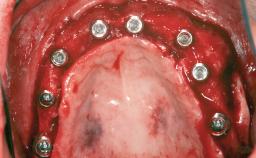

Ridge Preservation and Implant Placement for a Fixed Dental Prosthesis After a Car Accident

# of Teeth 6

# of Implants 4

Type of Implants One-Piece|Reduced-Diameter

Bone Augmentation Horizontal|Simultaneous|Sinus Floor Elevation|Staged